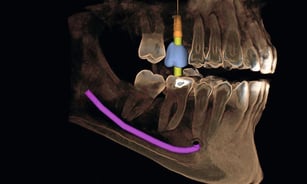

Implantologia Guidata

Tecnologie all'avanguardia per impianti dentali sicuri e duraturi.